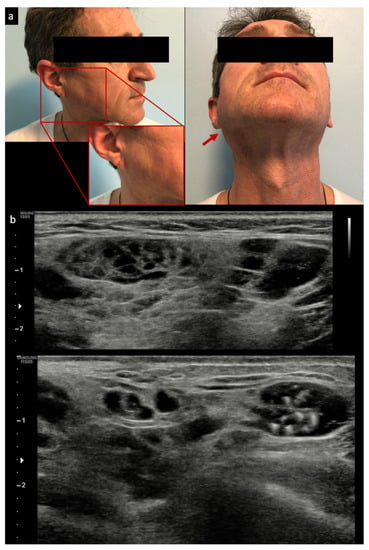

In the authors’ opinion, SGUS is also crucial to assist clinicians in the detection of glandular lymphoma, although few studies on this have been published to date. Lymphoma detection by SGUS in pSS has been described in some case series: they individuate, as expected, mostly MALT lymphoma (with two typical patterns described: the “linear echogenic strands pattern” also referred to as “multiple small hypoechoic nodules” or “tortoiseshell pattern”, and the “segmental pattern”/“multiple layer hypoechoic masses”) although no generally defined sonographic criteria for parotid lymphomas exist, as they present various non-specific US appearances [,,,]; see Figure 1.

Figure 1.

Examples of clinical parotid swelling (a) and appearance of mucosa–associated lymphoid tissue (MALT) lymphoma by ultrasound (b). Red arrow: Parotid swelling visible after cutaneous inspection.

However, in a recently published series, MALT lymphoma detected by SGUS also appeared as focal, hypoechoic, and dishomogeneous, with hypervascular areas with posterior acoustic enhancement, variable morphology and margins, and internal septa in half of the cases []. Importantly, only specific areas, and not all of the parotid gland, appeared to be involved by SGUS, which led to a new application of SGUS in pSS: to guide major SGs biopsy in definite glandular areas, usually in pSS patients with persistent parotid or submandibular enlargement.